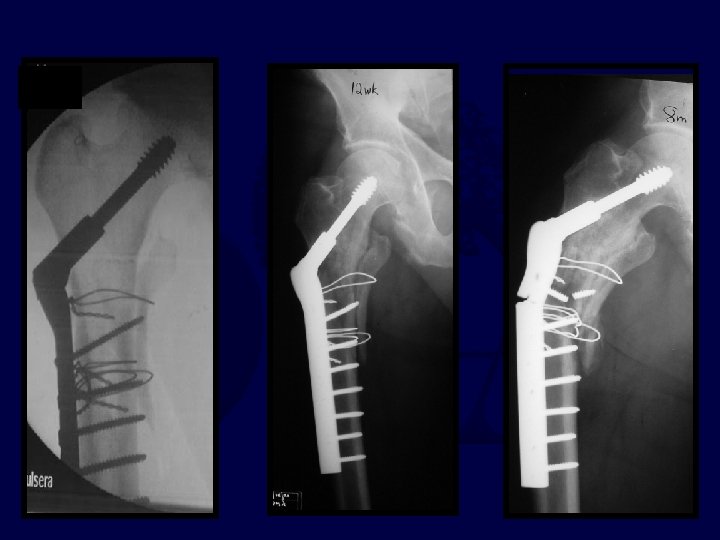

percutaneous reduction

Uneventful Healing, WBAT 6 wks 12 wks